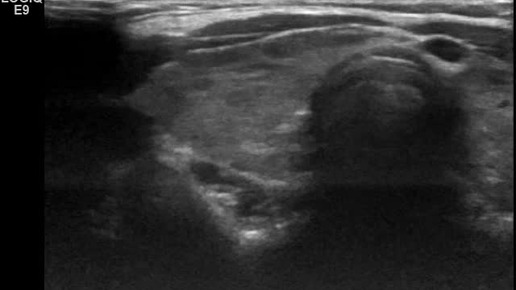

Видео к статье "Стратификация узлов щитовидной железы. TI-RADS-2"Адрес: https://dzen.ru/a/ZuUZLzUfMV_UqGyz